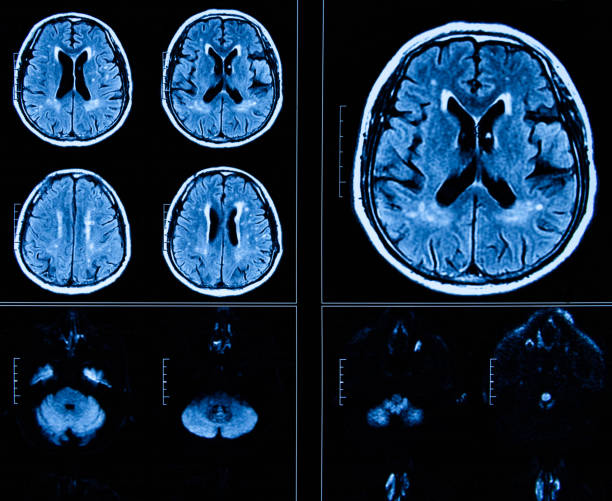

뇌졸중이란

뇌졸중은 뇌경색, 뇌출혈 등 뇌 관련질환을 이르는 전체적인 질병을 나타내는 단어입니다. 개별적으로 살펴보면 뇌경색은 뇌혈관이 막히거나 다른 곳에서 색전물질이 혈관을 통해서 전달이 되어서 혈관이 막힐 때 나타나는 병이며 뇌출혈은 작은 혈관이 파열되어 뇌동맥류 같은 질병들이 있는 상태에서 높은 압력으로 파열되면서 뇌실질에 출혈이 일어나는 경우를 말합니다

따라서, 뇌에 혈액을 공급하는 뇌혈관에 문제가 발생하면 산소, 영양분이 뇌에 제때 제대로 공급 하지 못해 뇌조직과 뇌세포의 기능이 떨어지면서 여러가지 증상이 나타나 골든타임이 중요한 뇌졸중이기 때문에 위에서 언급했듯 전조증상을 미리 잘 알고 있는 것이 중요합니다.